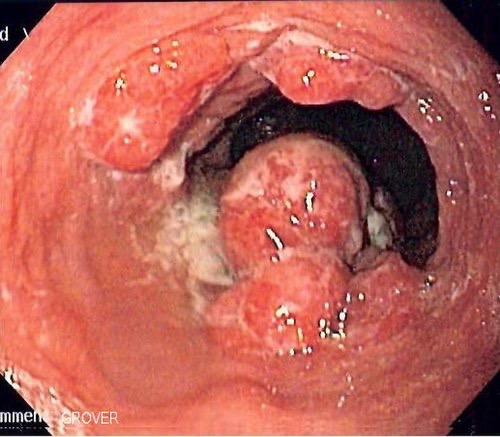

• 내시경 절제술: 조기 식도암(점막층에 국한)의 경우 내시경을 통한 점막하박리술로 치료가 가능합니다.